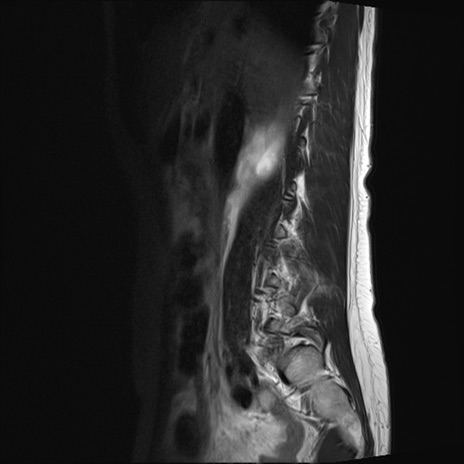

腰椎MRI

STIR(矢状断像)

横断像と矢状断像